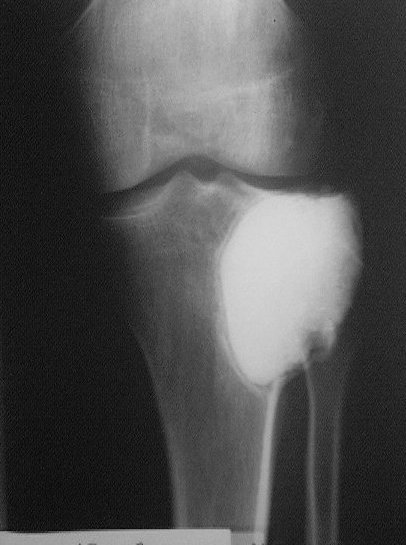

Около года назад больному 25 лет по поводу литической опухоли мыщелка б\б кости ( ОБК?)с выраженным болевым синдромом была произведенарасширенная открытая биопсия, экскохлеация опухоли.

В связи с неясностью диагноза до операции и отсутствия аллокости в тот момент интраоперационно было выполнено экспресс протезирование дефекта мыщелка акриловым цементом. Верхней стенкой дефекта была визуально неповрежденная суставная поверхность. Хрящевая пластина провисала - была выведена на уровень и "подперта" цементным спейсером. Больной осмотрен через год - ходит не хромая, сустав абсолютно спокойный, рентгенологически процедива опухоли нет. Хотелось бы услышать предложения по пластике дефекта - сроки, вид материала. Честно говорябоюсь трогать хрящ повторно.

Случай очень интересный! Увидеть бы снимки до операции. Можно обсудить состояние хряща "на цементе"-за счет чего он жив или там все-таки дефект? Щель сустава хорошая. Есть ли возможность проведения МРТ у больного?

Субхондральное эндопротезирование костным цементом при доброкачественных опухолях давно используется в институте им. Вредена. Редко бывают рецидивы (костный цемент, полимеризуясь, нагревается до 70 градусов). Сроки наблюдений благополучного исхода более 20лет.